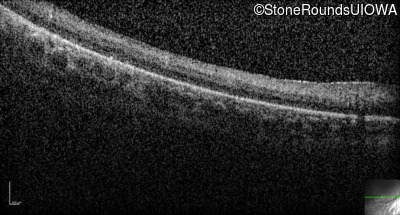

Optical Coherence Tomography - Right -

No Light Perception

Exemplar

Optical Coherence Tomography - Left -